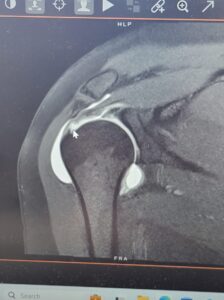

We kicked things off with Winter Retreat up at Story Book Lodge—nothing like sub-zero temps and youth-group worship to remind you you’re alive. We made it home just in time to ring in the New Year together, then Ethan headed back to Missouri while Lish, Riana, and Larissa escaped to Sedona for a Reeves sister’s trip. Red rocks, spa days, and zero boys allowed. They came home glowing, and a few days later Ethan flew back up so the whole crew could freeze together at Lake Metigoshe. The kids hit the hill with snowboards and Lish hit it with her shoulder. The end result: the kids shredded the slopes and Lish shredded her rotator cuff.

March brought shoulder surgery for Lish and a few surprises for the rest of us. Surprise 1: Lish can’t do all the household tasks with one arm tied behind her back. Surprise 2: I can do laundry, dishes, and basic house cleaning (who knew?). Surprise 3: Riana is a good cook. I had a little conversation with her boyfriend where I thought about telling him to follow Jacob’s example and work for 7 years before taking my newly discovered chef extraordinaire, but I didn’t. Then I had a little dinner conversation with Larissa where I thought about pointing out that I was eating enough for 2 people (hint, hint), but I didn’t because she beat me to the punch and casually announced that she was eating for 2 people. Best jokes I never told.